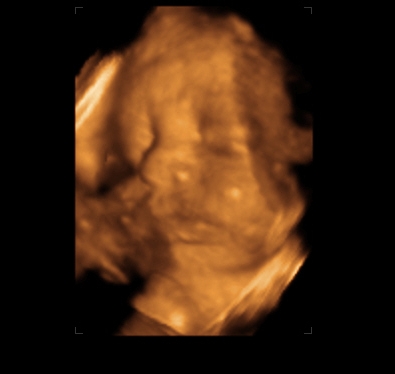

Verus, tündéri a kicsi pofi